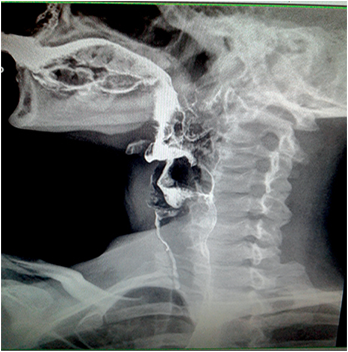

En una videodeglución se demostró la presencia de una membrana a nivel faringoesofágico que provocaba enlentecimiento en el pasaje del material de contraste (Figura 7). La VEDA objetivó a nivel cricofaríngeo una estrechez significativa, correspondiente con una membrana esofágica superior, la cual logró franquearse con el endoscopio, observándose restos de esta adheridas a dicho nivel y la mucosa de aspecto erosivo (Figura 8).